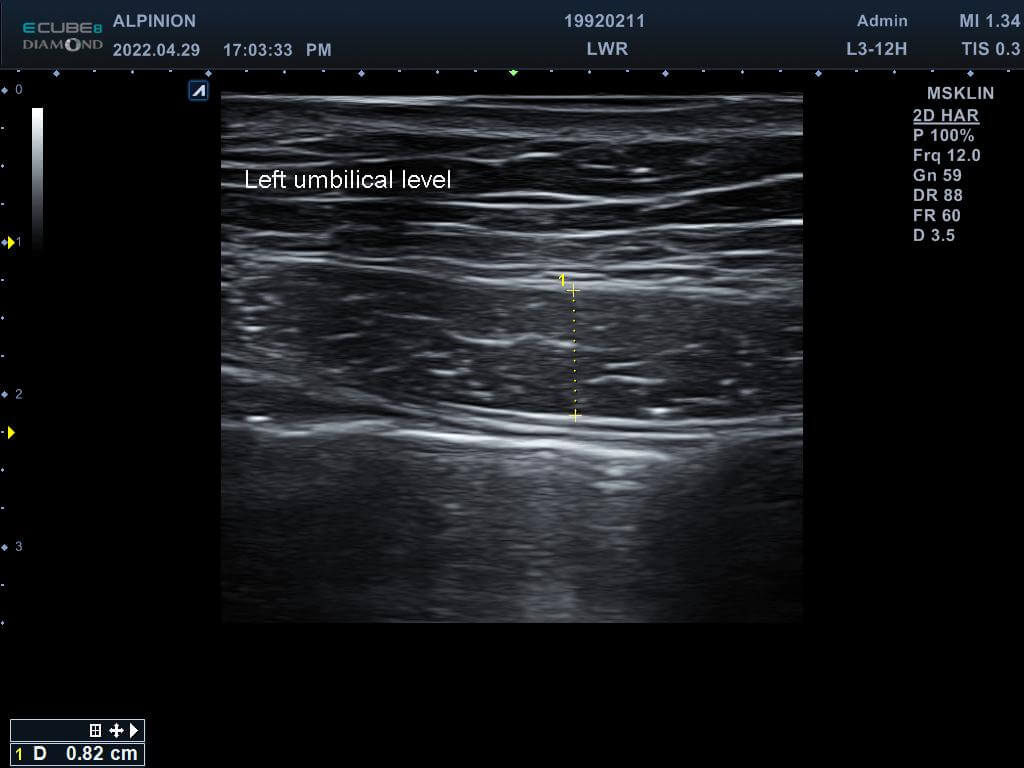

專業的醫師先在磁刺激前測量林小姐的腹直肌厚度,發現雙側的腹直肌分別為0.81cm(右側)與0.78cm(左側),同時雙側白線的距離也長達1.96cm,已經達到腹直肌分離的狀況。在使用了四周共8次的增肌減脂機後,雙側的腹直肌增厚為0.93cm(右側)與0.82cm(左側),同時雙側白線的距離減少1.46cm並明顯增厚,代表結締組織已經增生修復了。

增肌減脂(後)左側肚臍高度腹直肌增厚為0.82cm